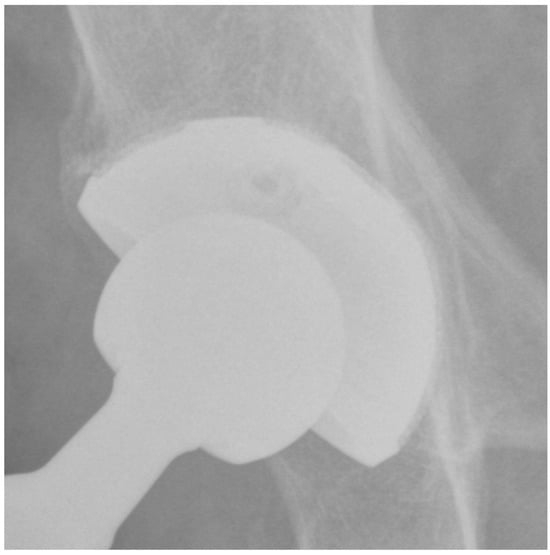

At the last follow-up, none of the patients showed signs of radiolucency. The presence of a superolateral buttress was detected in 95 (91.3%) patients. The presence of a medial stress shield was detected in 85 (81.7%) patients. The presence of radial trabeculae was detected in 70 (67.3%) patients, while the presence of an inferomedial buttress was detected in 75 (72.1%) patients. As a result, at least three signs (3 points) of osseointegration according to Moore et al. [] were observed in all patients. In detail, 40 (38%) patients showed a very well osseointegrated cup (5 points) (Figure 2), 40 (38%) patients showed a well osseointegrated cup (4 points), and 24 (24%) patients showed an osseointegrated cup (3 points). There were three (2.8%) cases of bone sclerosis around the acetabular component. Heterotopic ossifications occurred in five (4.8%) patients; all cases were classified as grade 1.

Figure 2.

Plain pelvis radiograph of a 79-year-old male patient at 4-year follow-up with 5 points according to Moore.